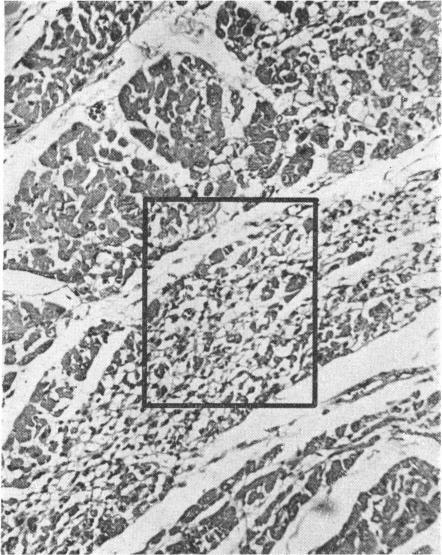

Focal myocytolysis, a form of myocardial damage, has been found to occur in about 8% of patients dying of intracranial lesions. Electrocardiographic abnormalities in patients with brain damage may be due to this. The cause of focal myocytolysis remains unknown, but if it could be prevented it might avert the patient's death from cardiac arrest or arrhythmia. Moreover, more than a minimal degree of this type of damage to the heart might make it unsuitable for transplantation.

局灶性心肌溶解是一种心肌损伤形式,已发现在约8%死于颅内病变的患者中出现。脑损伤患者的心电图异常可能归因于此。局灶性心肌溶解的病因尚不清楚,但如果能够预防,可能会避免患者因心脏骤停或心律失常而死亡。此外,这种类型的心脏损伤超过最小程度可能会使其不适用于移植。